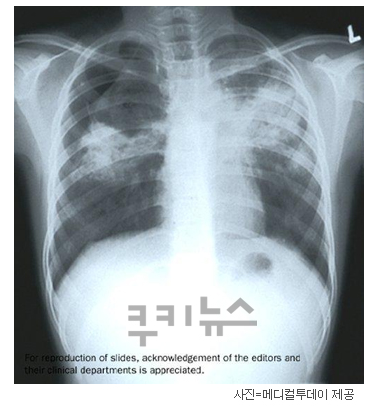

결핵은 옛날 가난한 시절의 병이고 후진국의 병이라는 오명이 있지만, 사실은 선진국 기준에서도 유병률 1위를 기록하고 있는 것이 바로 대한민국의 결핵입니다. 아직도 전 세계적으로 많은 사람의 목숨을 위협하고 있는 아-주 오랜 역사를 가진 질병이죠.

결핵은 코로나19도 마찬가지지만, 보균자여도 면역력이 좋으면 증상이 발현되지 않아 무증상으로 일상생활을 하게 되고, 증상이 발현된다면 주변에 쉽게 감염을 일으킬 수 있는 전염성이 매우 강한 질병입니다. 그래서 질병관리청에서는 지속적으로 결핵 검사의 중요성과 결핵 질병에 대한 오해를 해소 시키기 위한 캠페인을 꾸준히 진행해 오고 있습니다.